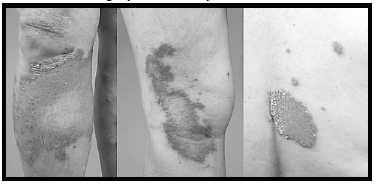

Paciente do sexo feminino, de 56 anos,

procedente de Cuiabá, refere aparecimento de

lesões isoladas em tronco e membros há 1 ano.

Refere que há 3 meses houve crescimento

progressivo das lesões, com acentuação do

eritema. Nega prurido e episódios de febre.

Quanto aos achados mais prováveis dos exames laboratoriais, assinale a alternativa correta.